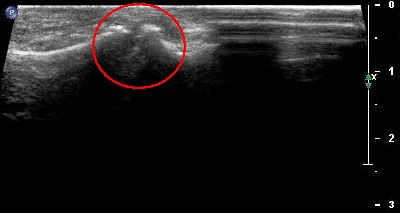

Cisti cisti 1